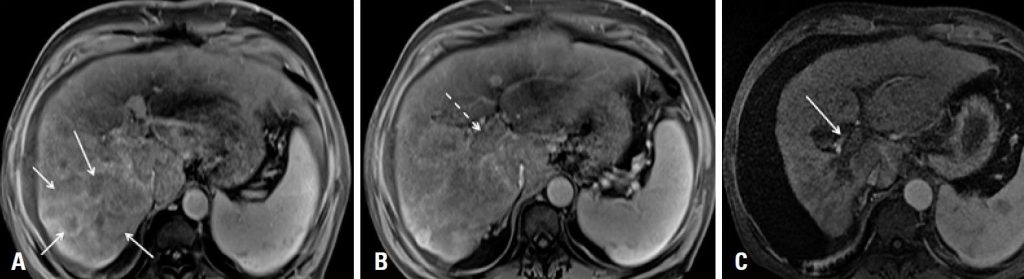

Aspects of images in magnetic resonance of liver tumors treated with transarterial selective internal radiotherapy with yttrium-90

Transarterial selective internal radiation therapy with yttrium-90, also known as radioembolization, is a therapy based on the administration of resin or glass microspheres loaded with the radioisotope yttrium-90, via selective arterial catheterization of tumor-feeding vessels. It is classified as a type of locoregional therapy and its main goal is to treat patients with primary or secondary hepatic lesions that are unresectable and not responsive to other therapies. Since it is a new technology still restricted to very few hospitals in Brazil, but used in patients throughout the country, it is necessary to demonstrate the main aspects of hepatic lesions treated with selective internal radiation therapy found in magnetic resonance imaging, and to make specific considerations on interpretation of these images. The objective of this report is to demonstrate the main aspects of magnetic resonance imaging of unresectable primary or secondary hepatic lesions, in patients submitted to transarterial selective internal radiation therapy.